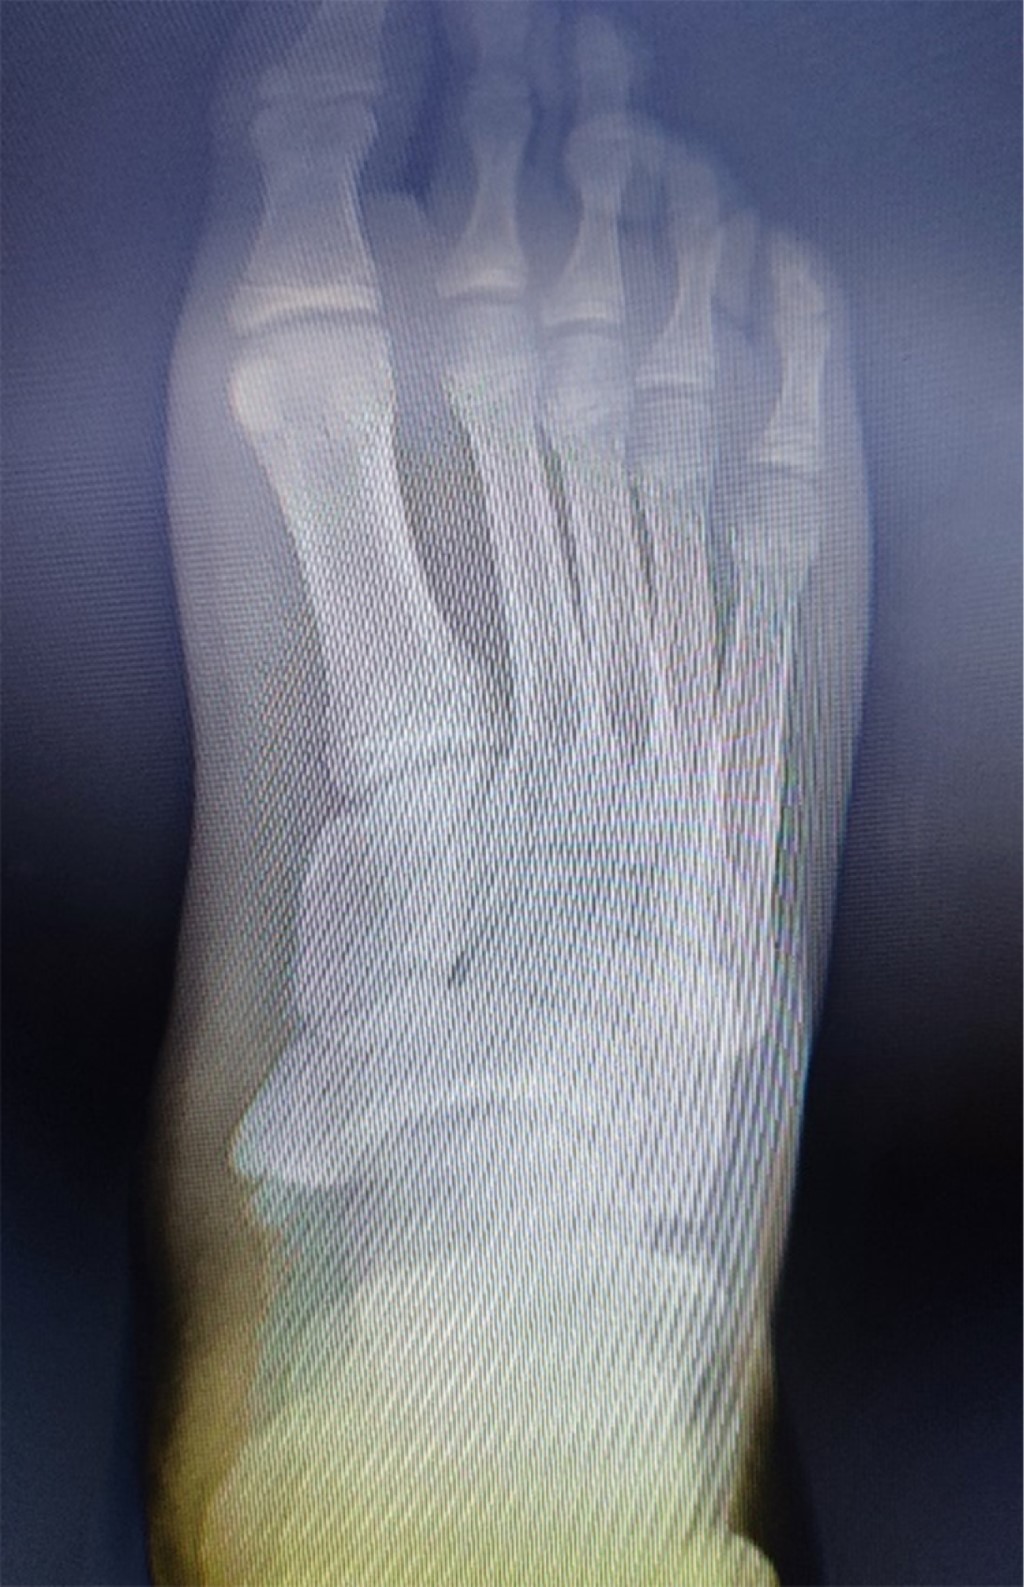

Masculino de 14 años que presentaba tres meses de dolor en cara interna de pie derecho, sin trauma (Figura 1). Al realizar la exploración se notó claudicación, talo valgo, pronación de antepié, dolor en escafoides tarsiano, sin pie plano. En la radiografía dorsoplantar y oblicua se evidenció prominencia unida al escafoides por puente óseo (tipo III) (Figura 2). Se optó por tratamiento conservador (descarga, analgésicos orales y tópicos) durante dos semanas, pero no hubo mejoría, por lo que se propuso cirugía.

Figura 2